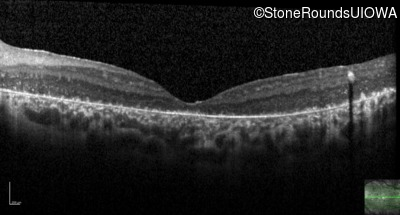

Optical Coherence Tomography - Left - 20/500

Exemplar / OCT Stack

OCT Stack